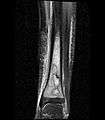

PA view of the left distal tibia showing a lytic lesion in the distal metaphysis with a narrow zone of transition more caudally with a faint sclerotic rim and a wide zone of transition more cephalad. Periostial reaction along the medial cortex indicates an aggressive lesion. Neoplasm such as Ewing sarcoma and osteomyelitis could both have this plain radiographic appearance. Staphylococcus was recovered at surgery.